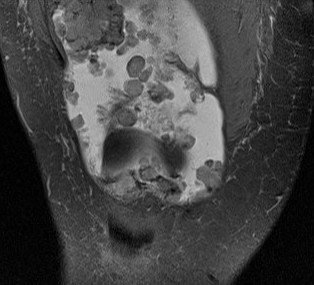

MRI

Synovial Proliferation

Soft tissue lesions same signal intensity as cartilage

Synovial chondromatosis

Synovial osteochondromatosis